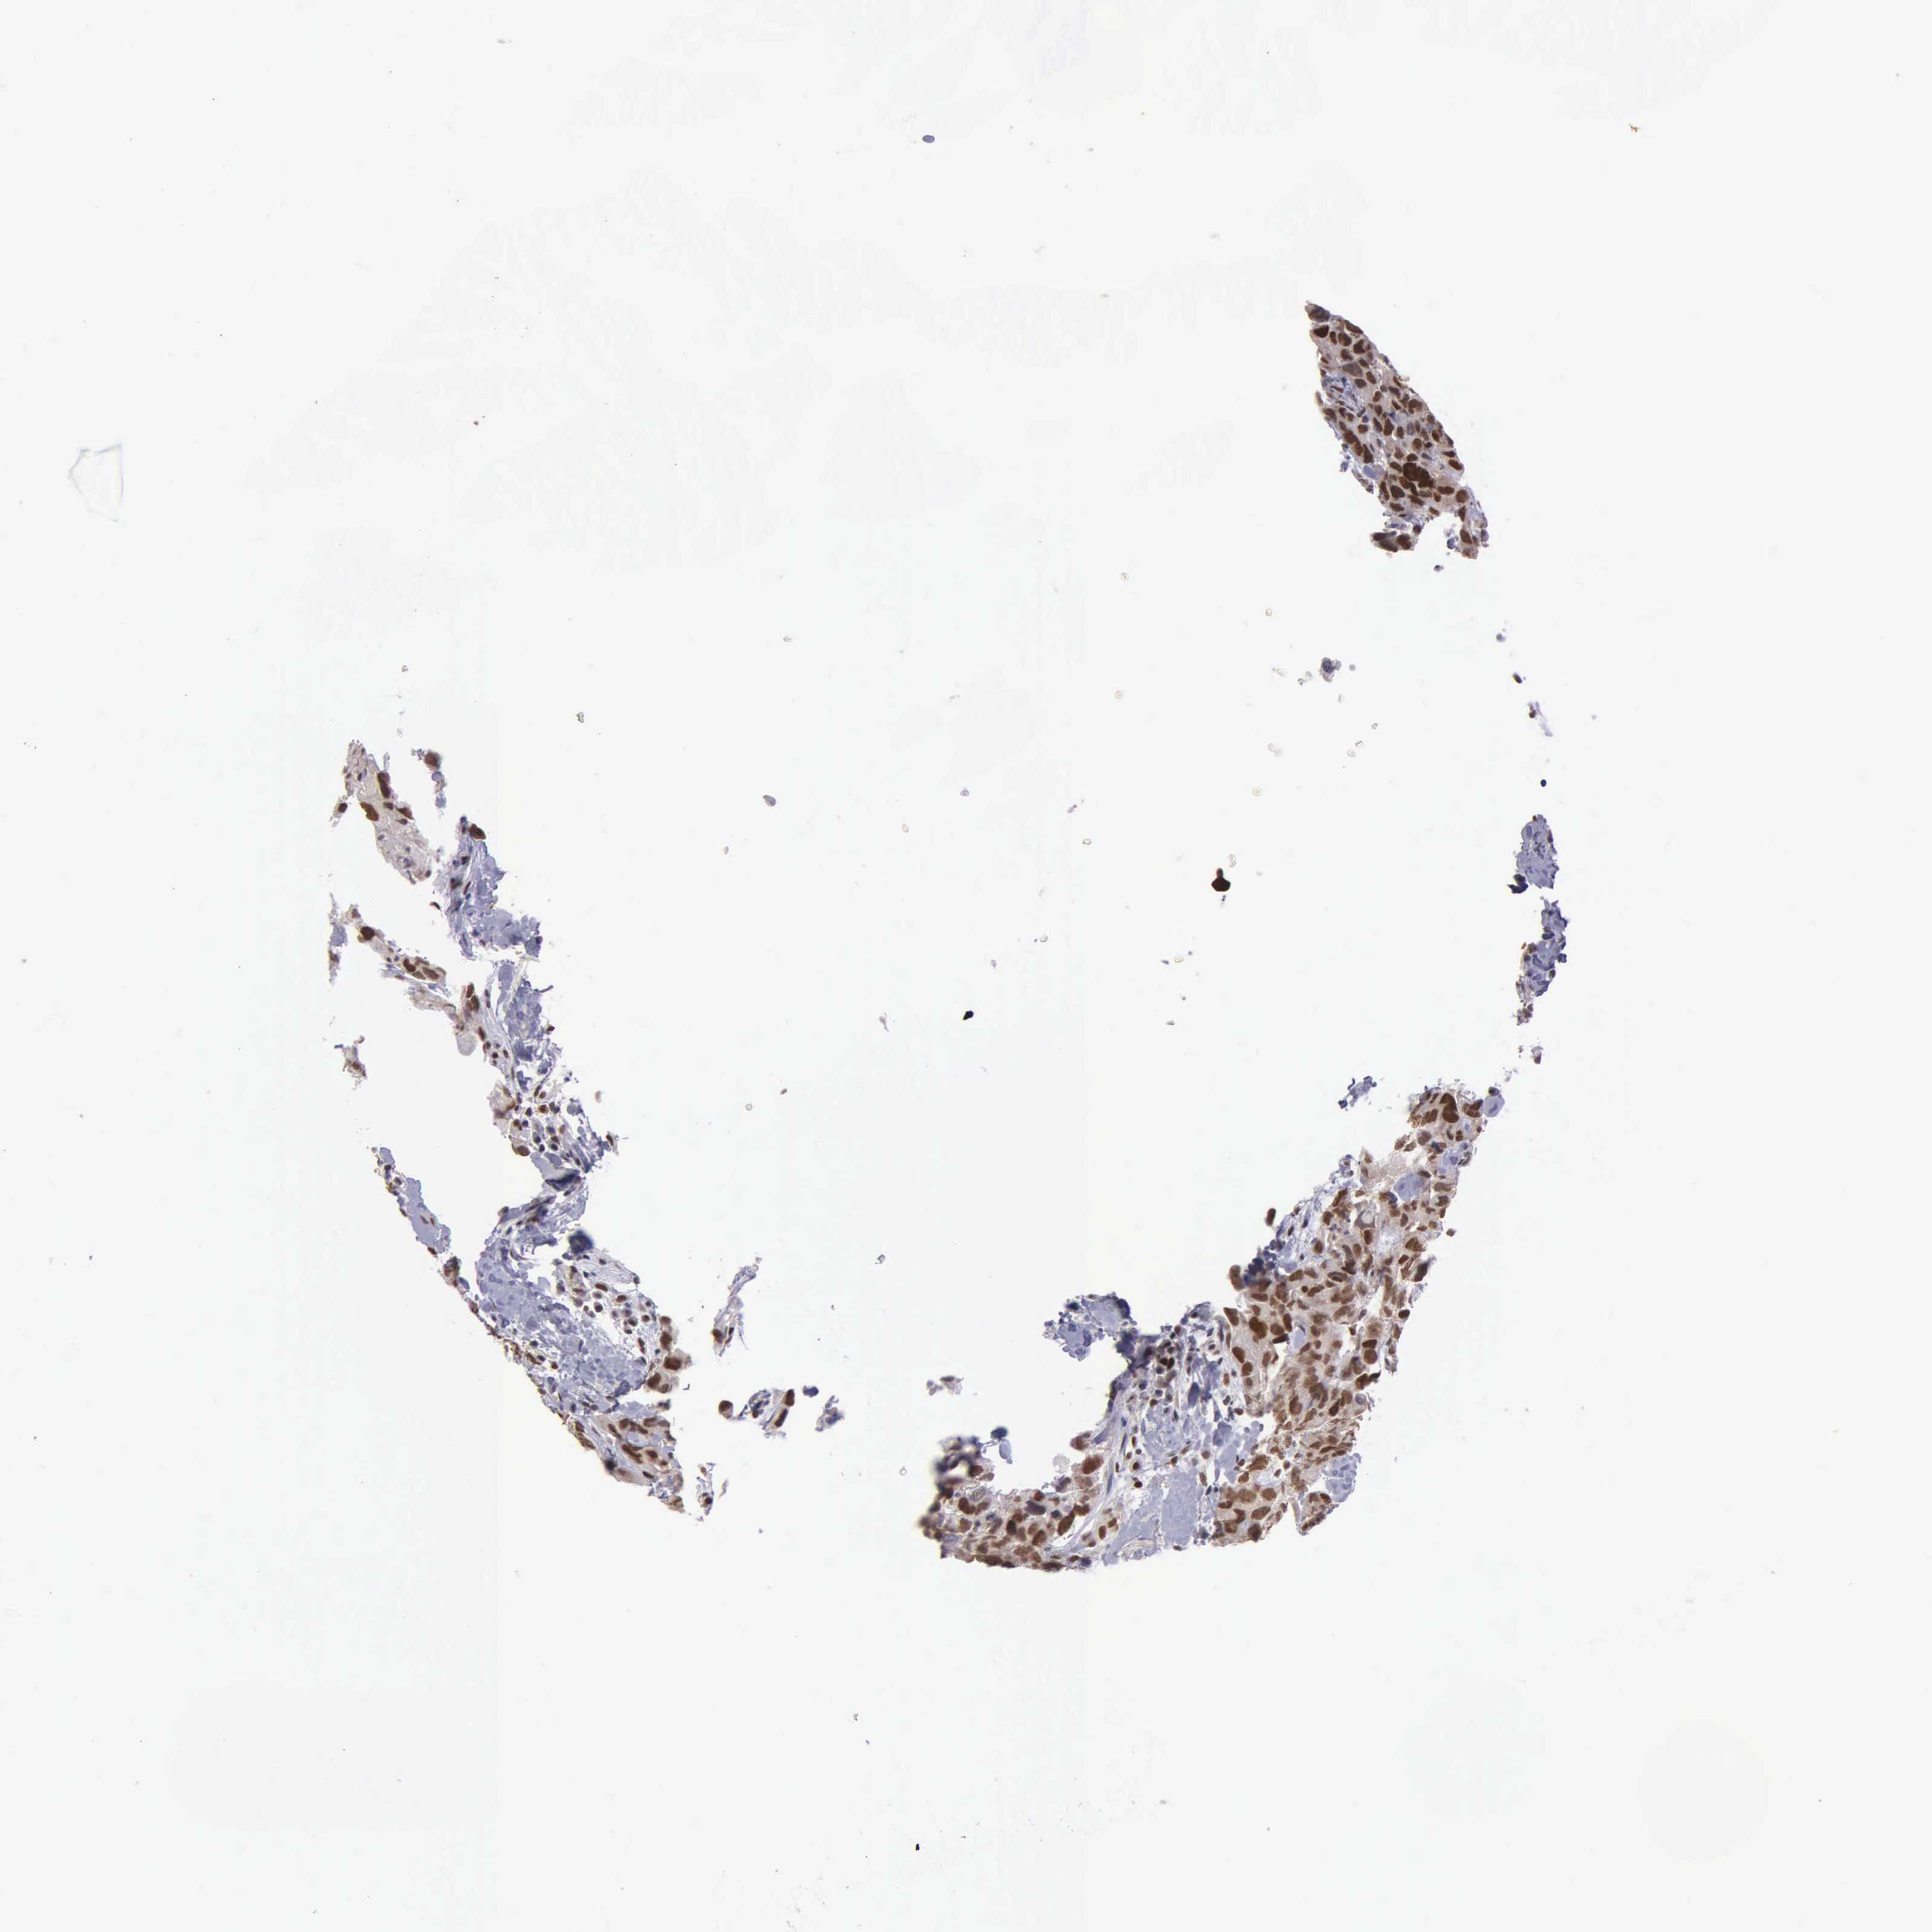

BRCA TCGA BRCA VALIDATION PROTEIN EXPRESSION

Breast cancer

Human cancer

Breast invasive carcinoma